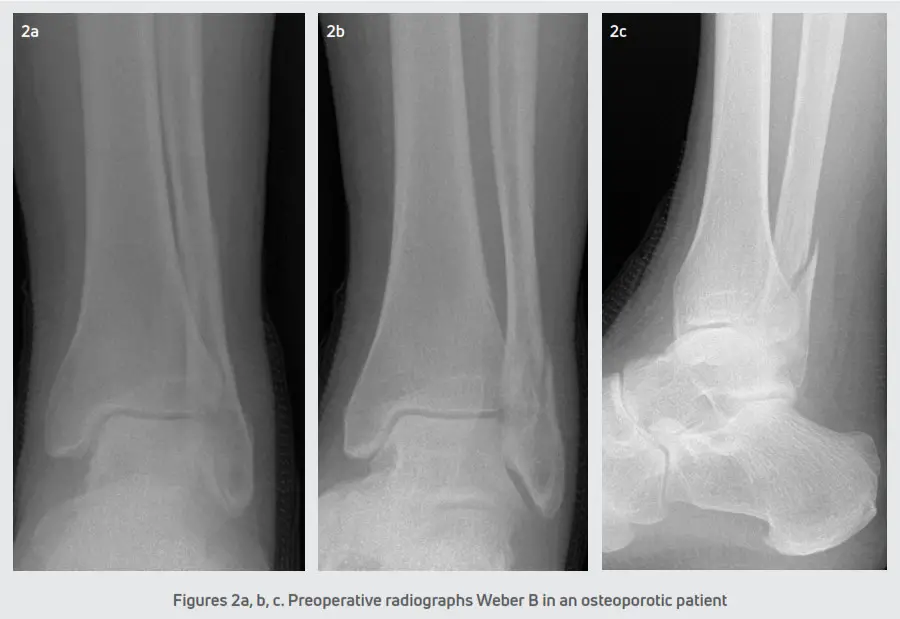

All the patients were seen at the senior author’s private practice for an evaluation. Patients were splinted and initially kept non-weight bearing until the scheduled date for surgery. Open reduction and internal fixation of the ankle fractures were performed within 1 and 2.5 weeks post-injury depending on the edema and condition of the soft tissue envelope at the initial presentation. Each patient received preoperative radiographs. (Figures 2 and 3) Also, additional radiographs were taken at postoperative visits typically at weeks 4, 8, and 12. During each postoperative appointment, the fracture sites were examined for clinical signs of healing.

The incisions were closed in a standard layered fashion and a sterile, compressive dressing was applied. All patients were immobilized with a posterior splint and were initially non-weight bearing. Patients were seen for the first postoperative visit within 5-6 days for a wound evaluation. A sterile dressing and posterior splint were reapplied and patients returned at two weeks for suture removal. The postoperative course consisted of non-weight bearing in a posterior splint for 2-3 weeks. In ankle fractures with a stable syndesmosis (Figure 4), patients were transitioned into a CAM boot at 3 weeks and began protected partial weight-bearing with physical therapy. After 6 weeks, patients were transitioned to a supportive athletic shoe with an ankle brace and the final follow-up was at 12 weeks. In ankle fractures that required syndesmotic repair (Figure 5), patients were transitioned into a CAM boot and began protected partial weight-bearing at approximately 8-10 weeks. Patients were progressed into normal shoe gear at 12 weeks and aggressive physical therapy. Patients were discharged at 4-6 months and followed up as needed.